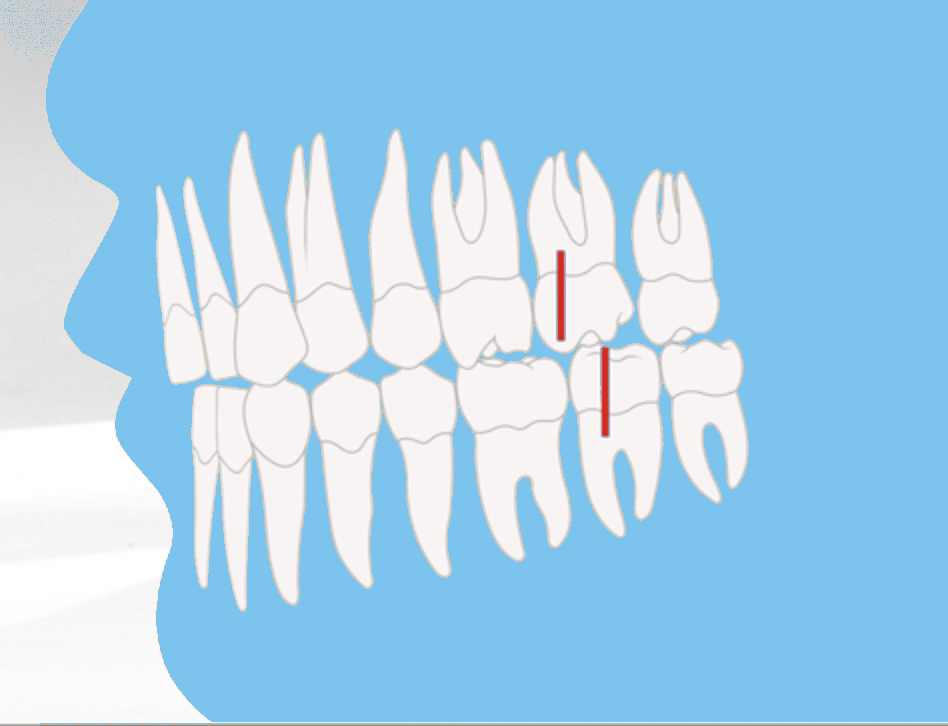

Das Ordnungssystem der Zahn- und Kieferfehlstellungen: Die Angle-Klassen

Die Angle-Klassen sind ein international anerkanntes Ordnungssystem, um Zahn- und Kieferfehlstellungen systematisch zu diagnostizieren und zu bewerten. Grundlage ist die Lagebeziehung der ersten bleibenden großen Backenzähne – der sogenannten 6-Jahr-Molaren – von Ober- und Unterkiefer zueinander. Entwickelt wurde das Klassifikationssystem bereits Anfang des 20. Jahrhunderts von dem amerikanischen Kieferorthopäden Edward H. Angle. Trotz zahlreicher moderner Diagnosetechniken ist es bis heute ein fester Bestandteil der kieferorthopädischen Beurteilung.

Angle-Klasse I: Der Neutralbiss

Die Angle-Klasse 1 beschreibt ein reguläres, gesundes Gebiss ohne Abweichungen in der Bisslage. Man spricht auch von einem Neutralbiss. Hierbei trifft der vordere Höcker des ersten großen Backenzahns im Oberkiefer genau in die Lücke zwischen den beiden Höckern des gegenüberliegenden ersten großen Backenzahns im Unterkiefer.

In dieser Stellung beißen die Zähne von Ober- und Unterkiefer harmonisch aufeinander, wodurch sowohl die Kaufunktion als auch die Ästhetik optimal sind. Auch das Gesichtsprofil wirkt ausgeglichen, da keine Abweichungen in der Kieferlage vorliegen.

Angle-Klasse II: Überbiss (Distalbiss)

Die Angle-Klasse II beschreibt einen Überbiss bzw. Distalbiss. In diesem Fall beißt der vordere Höcker des ersten großen Backenzahns im Oberkiefer vor den entsprechenden Backenzahn im Unterkiefer. Dadurch verschiebt sich der Zusammenbiss zu weit nach hinten, was funktionelle und ästhetische Probleme verursachen kann.

Je nach Stellung der oberen Schneidezähne unterscheidet man zwischen Angle-Klasse II/1 und Angle-Klasse II/2.

Angle-Klasse II/1: Nach außen gekippte Schneidezähne

Bei der Angle-Klasse II/1 sind die oberen Schneidezähne deutlich nach außen geneigt. Diese Fehlstellung führt häufig zu Schwierigkeiten beim Abbeißen und beeinträchtigt zusätzlich das Gesichtsprofil. Durch die nach vorne stehenden Schneidezähne wirken die Zähne optisch oft größer – im Volksmund auch als “Hasenzähne” bezeichnet.

Angle-Klasse II/2: Nach innen gekippte Schneidezähne

Die Angle-Klasse II/2 beschreibt ebenfalls einen Distalbiss, unterscheidet sich jedoch in der Stellung der Schneidezähne. Im Gegensatz zur Angle-Klasse II/1 sind die oberen Schneidezähne hier nach innen gekippt.

Diese Form der Fehlstellung wirkt sich sowohl auf die Zahnfunktion als auch auf die Gesichtsästhetik aus. Besonders auffällig ist, dass das Kinn im Verhältnis zum Oberkiefer zurückliegt, wodurch das Gesichtsprofil disharmonisch erscheint.

Angle-Klasse III Vorbiss (Mesialbiss / Progenie)

Die Angle-Klasse III beschreibt eine Vorbiss-Fehlstellung, die auch als Mesialbiss oder Progenie bezeichnet wird. Dabei steht der Oberkiefer zu weit zurück bzw. der Unterkiefer zu weit nach vorne.

Charakteristisch ist, dass der vordere Höcker des ersten großen Backenzahns im Oberkiefer hinter den entsprechenden Backenzahn im Unterkiefer beißt. In der Folge liegen die unteren Schneidezähne vor den oberen Schneidezähnen. Dies führt zu funktionellen Einschränkungen beim Abbeißen und Kauen.

Auswirkungen auf das Gesichtsprofil

Neben den funktionalen Problemen wirkt sich die Angle-Klasse III auch stark auf die Gesichtsästhetik aus. Typisch ist ein vorstehendes Kinn, wodurch das Gesicht häufig streng oder „grimmig“ erscheint. Ohne Behandlung können sich die funktionellen Probleme verschlimmern und die Fehlstellung im Erwachsenenalter deutlicher ausgeprägt zeigen.

Infografik: Die Angle-Klassen (I - III)

Angle-Klasse I

Neutralbiss - reguläres Gebiss Ober- & Unterkiefer im Gleichgewicht Gesichtsprofil harmonisch

Angle-Klasse II

Überbiss / Distalbiss Oberkiefer zu weit vorne Unterkiefer zurück

Angle-Klasse III

Vorbiss / Mesialbiss Unterkiefer zu weit vorne Kinn wirkt vorstehend